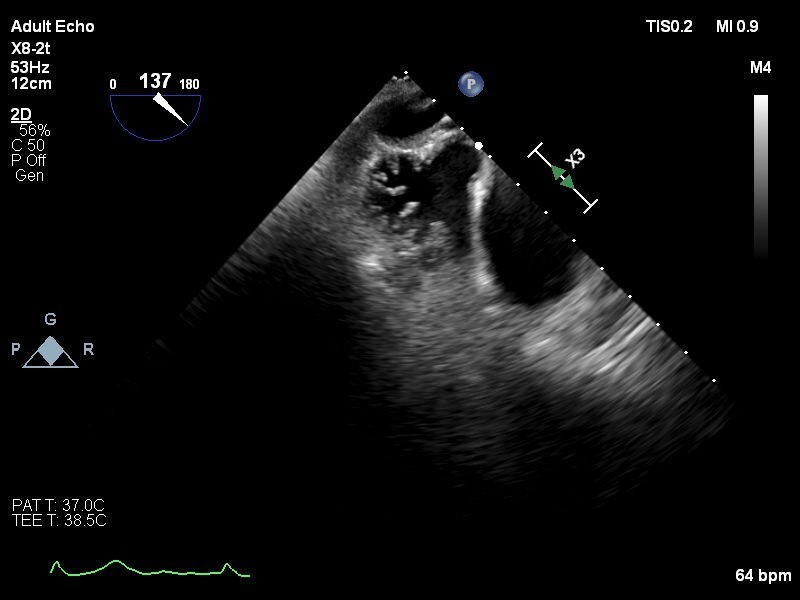

【症例】

80歳代 男性

糖尿病, 高血圧症, 脂質異常症, 持続性心房細動, 食道癌, 胃癌(2020/2), 大腸癌術後(2001,2009), 慢性腎臓病, 高度貧血, TAVI(2019/12 Sapien3 26mm), 冠動脈バイバス術後(2018/04), ラクナ梗塞

しかし出血リスク高く、今回左心耳閉鎖治療予定となる